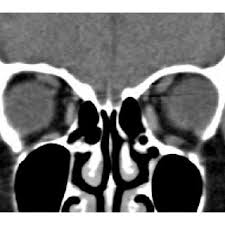

Computed tomography (CT) of the orbit can demonstrate relative localization of extra ocular muscle with respect to the globe and presence of any slippage of extra ocular muscle in patient of myopic strabismus fixus.